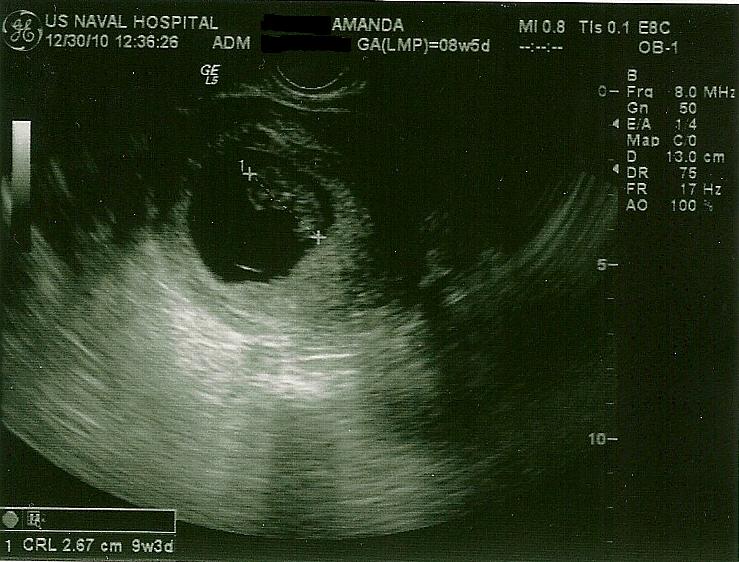

Really good day! Got to see the babies again-they are still there and healthy!-and woohoo, I gained a pound!! Huge accomplishment since it's been a struggle so far, and we have a goal of 15-20 to reach by the 24 week mark.

Here are the babies! Measuring well (actually a little ahead of what we would have expected) and heartbeats were higher than last time-180 for A and 176 for B.

Baby A-this one you can see the best. You can see little fingers off to the left, his or her knee bent and little toes! Amazing!

Baby B-we actually got to see this one move around a little while getting ready for this shot! So sweet! I don't remember seeing Maya move around on ultrasound till her anatomy scan.

These next ones are mostly of Baby B, but you can see A off to the left.

Both of them together (sweet relief to see two! I was so worried (of course) that one would be gone!)